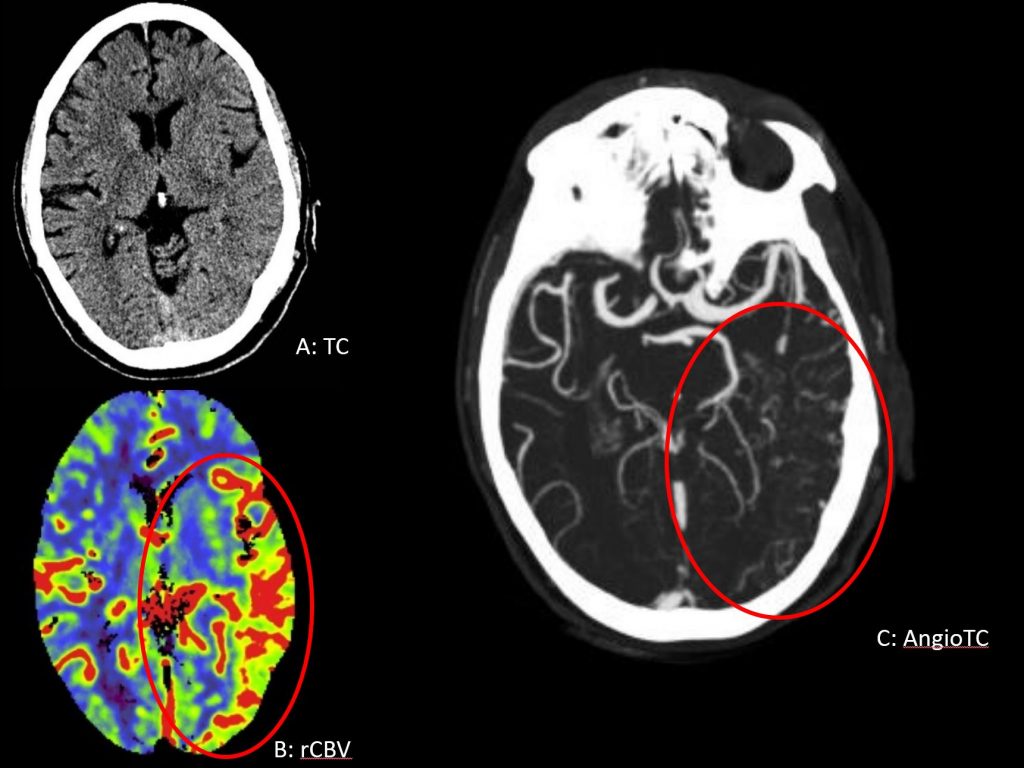

TC multimodal (A, B): Borramiento de surcos en región temporoccipital izquierda con aumento del rCBV asociado y estructuras vasculares anómalas en angioTC (C).

La sobrecarga venosa del territorio superficial posterior de la ACM izquierda (C) se puede deber a:

– fistula dural en dicha localización

– trombosis del seno transverso y/o sigmoideo izquierdo, que en este caso se encontraban permeables.